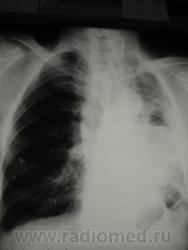

Да, вроде бы и легкое уменьшено, и средостение уехало. А что там за огромный абсцесс? Не опухоль же распадается? Такого с уровнем не должно быть.

случай давнишний, у пациента подтвержденный центральный рак, оперировать не стали, пришел когда хуже почувствовал себя, я ему тоже написала абсцесс. а куда он делся дальше незнаю((((((

И не просто абсцесс, возможно, еще и с задне-базальным осумкованным выпотом.

Несколько иллюстраций к вышесказанному.